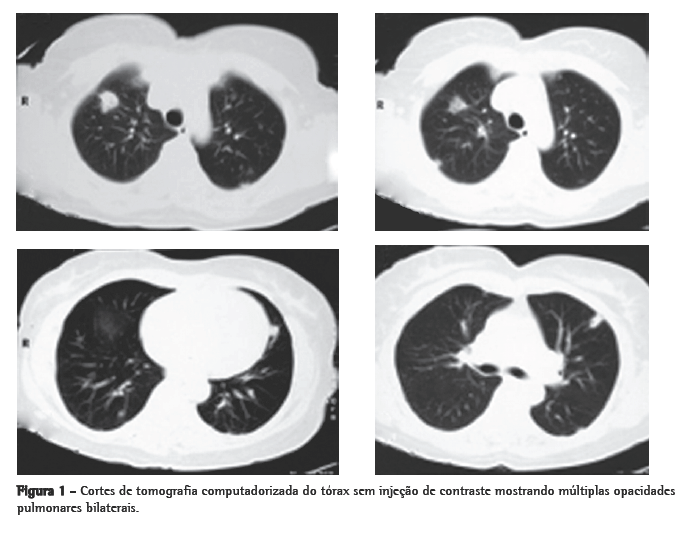

Mulher de 56 anos, branca, procurou o serviço de emergência devido à tumoração em região cervical à direita, dolorosa, há 5 dias. Apresentava tosse seca e febre alta há 3 dias. Negava tabagismo. Era hipertensa e diabética e havia tido um infarto do miocárdio há 3 anos. Na admissão, a paciente apresentava-se desidratada, afebril (temperatura axilar, 36,7°C), eupnéica, com tumoração cervical dolorosa à direita. Os exames laboratoriais revelaram velocidade de hemossedimentação aumentada (92 mm). A ecografia cervical mostrou trombose em VJI direita, sendo iniciada anticoagulação no quarto dia de internação. A radiografia de tórax demonstrou pelo menos dois nódulos no pulmão esquerdo, um aparentemente escavado e outro com 18 mm de diâmetro na base, além de lesão irregular com 25 mm de diâmetro no lobo superior direito. Foi realizado ecocardiograma transesofágico para descartar a hipótese de endocardite, o qual não demonstrou presença de vegetações. Devido à hipótese de pneumonia, foi iniciado tratamento empírico com 500 mg de cefuroxima, via oral, a cada 12 h. A tomografia de tórax revelou múltiplas opacidades bilaterais, de aspecto sugestivo de implante metastático (Figura 1). Prosseguindo a investigação, a paciente foi submetida à broncoscopia flexível, cujos achados endoscópicos foram normais. A análise microbiológica do lavado broncoalveolar para pesquisa de bacilo álcool-ácido resistente e fungos, assim como seu estudo citopatológico e culturas, foram negativos. Com a hipótese de neoplasia metastática, a paciente foi submetida à biópsia pulmonar cirúrgica, cujo exame anatomopatológico mostrou inflamação supurativa crônica abscedada em organização em parênquima pulmonar. Frente à hipótese de síndrome de Lemierre devido à trombose jugular associada à embolia séptica pulmonar, a paciente foi questionada sobre a ocorrência de amigdalite no início do quadro. A paciente não recordava, mas a filha lembrou que a mesma havia usado 500 mg de amoxicilina, via oral, a cada 8 h por 10 dias, para tratamento de amigdalite alguns dias antes da internação. Na admissão hospitalar, a paciente recebeu um curso de cefuroxima (750 mg endovenoso a cada 8 horas por 7 dias) concomitante a azitromicina (500 mg via oral por 5 dias),que, por persistência da febre, foi modificado para cefepime (1.000 mg a cada 12 horas por 7 dias).

O envolvimento pulmonar nesta síndrome é extremamente comum (até 97% dos casos). As lesões pulmonares podem se manifestar já no primeiro dia de sepse. Podem ocorrer dor pleurítica intensa com dispnéia e, freqüentemente, hemoptise. Estertores crepitantes localizados e atrito pleural podem ser auscultados. A radiografia de tórax mostra tipicamente múltiplas opacidades bilaterais e pequenos derrames pleurais. É possível detectar-se cavitação já na primeira radiografia. Pode haver rápida progressão das lesões, mesmo na vigência de antibióticos. Empiema desenvolve-se entre 10% a 15% dos casos. Abscesso, pneumotórax e pneumatoceles são descritos. Com administração de contraste, ocorre realce periférico das lesões com áreas centrais de redução da atenuação. O diagnóstico diferencial é com pneumonia (bacteriana aguda, atípica, aspirativa e estafilocócica).(1,2,11-14)